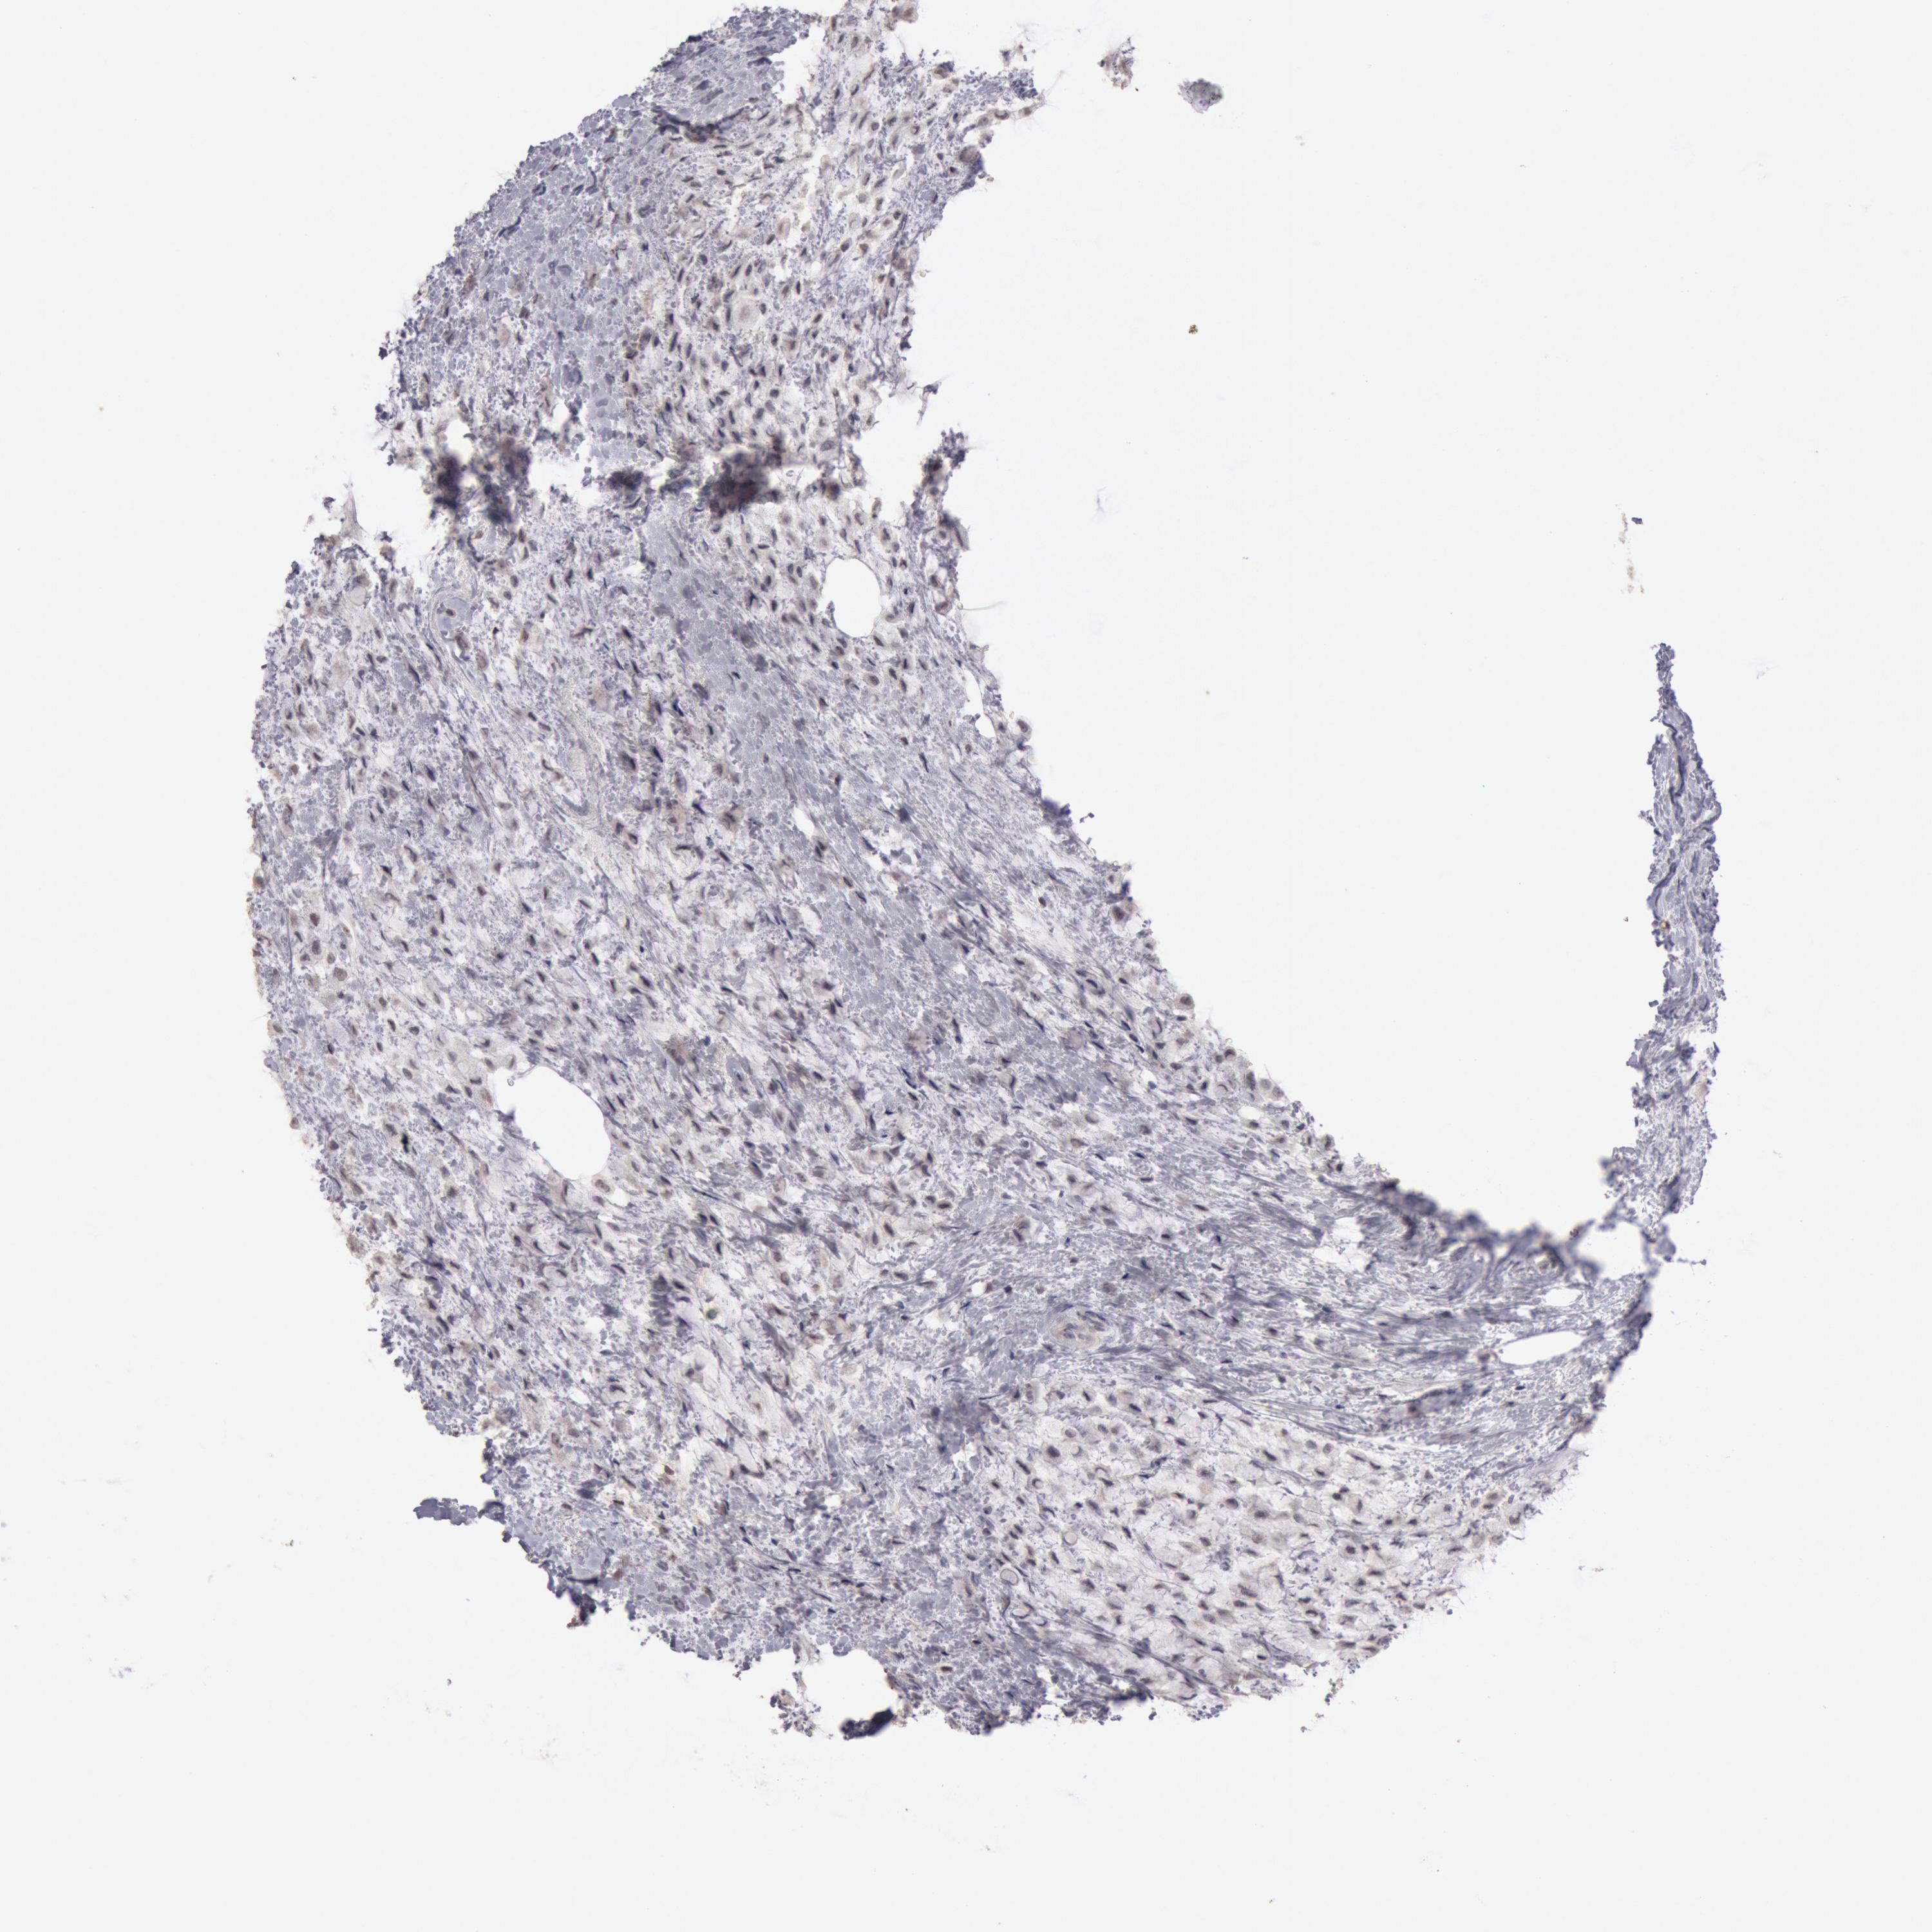

BRCA TCGA BRCA VALIDATION PROTEIN EXPRESSION

Breast cancer

Human cancer